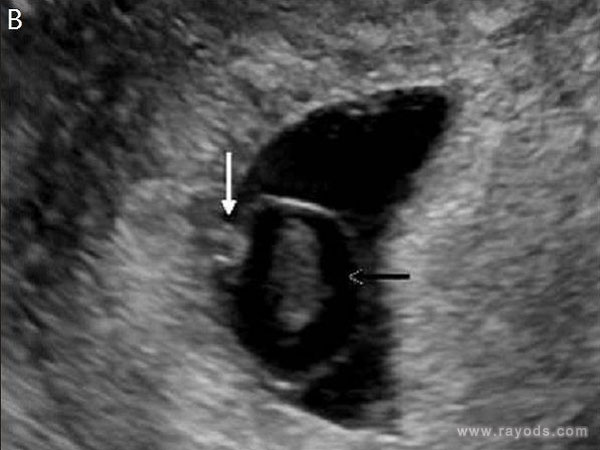

通常来说卵黄囊的正常范围大概在3-8mm之前,一般不会超过8mm,超过或者低于这个范围都属于异常,比较容易引起流产,对于绝大多孕妇,怀孕6周左右做B超检查,就可以看到宫腔内由卵黄囊。

卵黄囊的大小通常都是以它的长和宽来判断,临床上一般以横径作为判断其标准大小,卵黄囊会随着孕周的推移,出现一个增大的情况,在增加到一定值的时候,又会慢慢变小直到消失,具体的对照表如下:

孕周 胎儿大小 卵黄囊大小 4周 0.2cm 胚胎很小,B超下看不见其大小 5周 0.4cm 羊膜腔扩大,可见小卵黄囊,约占宫腔不到1/4,约3mm左右 6周 0.85cm 胎儿分化,卵黄囊发育变大,约4mm 7周 1.33cm 胚胎初具形态 胎芽及胎心可见,卵黄囊约5mm 8周 1.66cm 胎儿形态及胎动清楚可见,约5-6mm 10周 2.83cm 胎儿各器官均已形成,卵黄囊囊壁开始退化,逐渐变小 12周 4.58cm 外生殖器初步发育,胎盘发育形成,卵黄囊消失